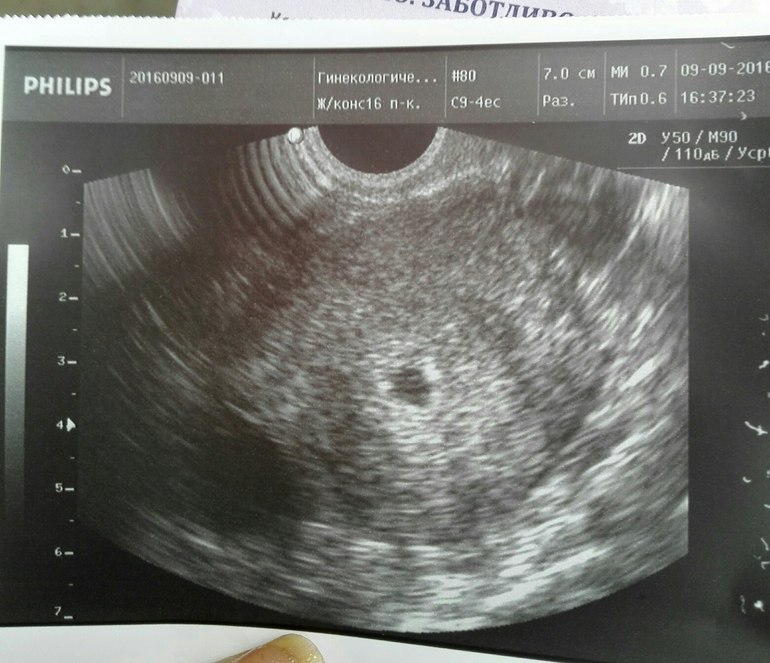

Вчера сделала третий анализ ХГЧ - 2137. И побежала к гинекологу, увидев мою динамику, врач повела меня на УЗИ, ватными ножками дошла до кабинета, трясущимися ручками сняла джинсы, секунд 10 на кушетке и слова врача ,,жду тебя у себя, а это тебе,,

А там моя капелька))) Господи, она в матке! Врач сказала, что все в порядке. Назначила мне дюфастон, но-шпу и сдать гемостазиограмму, расширенную, ещё я пожаловалась на плохое самочувствие, все кругом болеют, голова раскалывается, сказала только гриппефрон. И следующая наша встреча через 10 дней, будем рассматривать капельку. Сейчас смысла нет. Сегодня весь день в кровати, температура 37,2, но ни соплей, ни кашля, а состояние разбитое. Никакого токсикоза не было и нет, грудь вчера болела сильней, сегодня нет. Пью чаи, клюквенные морсы, имбирный чай. О плохом не думаю...

Спасибо) Срок по последним месячным 5 недель 4 дня. Размер не знаю...Ничего она измерять не стала, гинеколог решила уже в 7 недель посмотреть всё и измерить, сейчас ничего видно, да и аппарат УЗИ в ЖК самый простенький, решила нервы мне не трепать) Главное, чего я боялась - внематочная беременность, мы исключили. Поэтому будет ещё один шаг - УЗИ при сроке, который уже будет информативен. Если всё будет хорошо, то пойдём дальше))